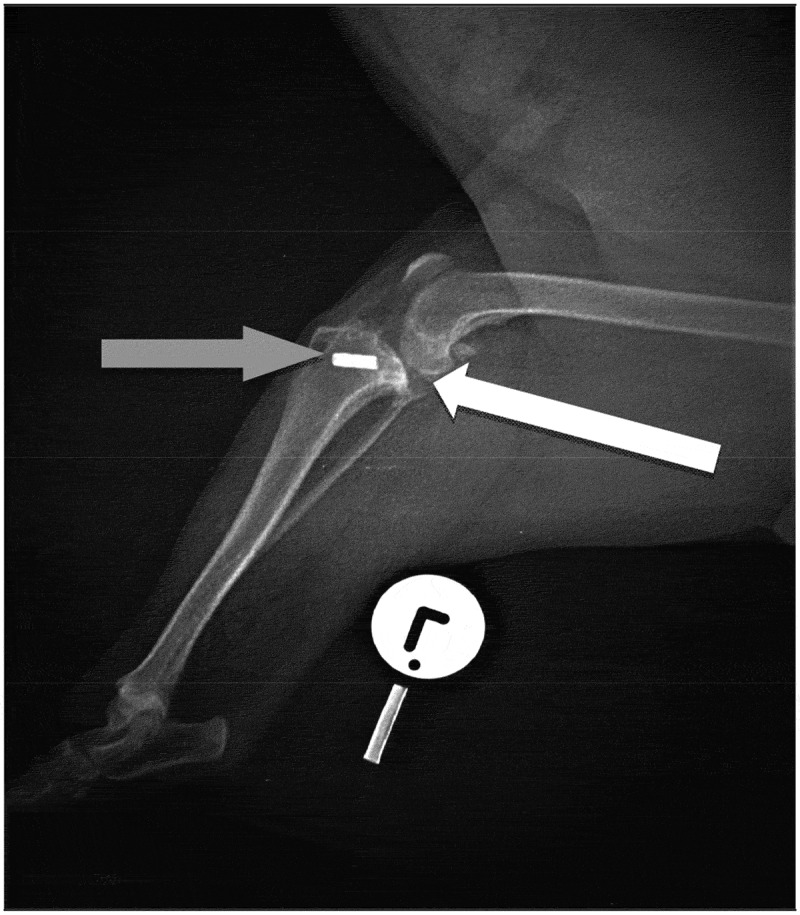

我们描述了一例慢性淋巴浆细胞性绒毛结节性滑膜炎(CLPVNS)与颅十字韧带(CCL)疾病相关的10岁绝育杰克罗素梗母狗。这只母狗被送到兽医诊所,患有严重的、非负重的、急性左后肢跛行。这只母狗先前曾使用外侧腓骨缝合(LFS)技术对同一关节的膝关节CCL疾病进行手术治疗。自治疗以来,患者有间歇性左后肢非负重性跛行史,可通过非甾体抗炎药(NSAIDs)治疗。触诊和操作受影响的膝关节引起剧烈疼痛。没有其他临床或矫形异常。受影响的膝关节的正交x线片显示中度退行性关节疾病和股骨外侧髁外侧和腓骨头部的溶骨性病变。从关节处抽吸的液体培养细菌生长阴性。细胞学结果怀疑为CLPVNS。探查性关节切开术、滑膜切除术、清创术及关节灌洗术。获得关节的骨和滑膜活检样本并提交实验室进行组织病理学确诊。细胞学初步诊断CLPVNS,活检标本病理证实。本病例报告强调了在伴有CCL疾病的跛行犬中检查CLPVNS的重要性,因为报告显示它被低估或误诊。

We describe a case of chronic lymphoplasmacytic villonodular synovitis (CLPVNS) associated with cranial cruciate ligament (CCL) disease in a 10-year-old spayed Jack Russell Terrier bitch. The bitch was presented to a veterinary clinic with severe, non-weight bearing, acute left hindlimb lameness. The bitch had previously been treated surgically for stifle CCL disease of the same joint, using the lateral fabellar suture (LFS) technique. Since the treatment, the patient had a history of intermittent left hindlimb non-weight bearing lameness that was manageable with nonsteroidal anti-inflammatory drugs (NSAIDs). Palpation and manipulation of the affected stifle elicited severe pain. There were no other clinical or orthopaedic abnormalities. Orthogonal radiographs of the affected stifle revealed moderate degenerative joint disease and osteolytic lesions on the lateral aspect of the lateral femoral condyle and the head of the fibula. A fluid aspirate from this joint was negative for bacterial growth on culture. Cytology results were suspicious for CLPVNS. Exploratory arthrotomy, synovectomy, debridement and lavage of the affected joint were performed. Bone and synovial membrane biopsy samples of the joint were obtained and submitted to a laboratory for a histopathological confirmatory diagnosis. CLPVNS was tentatively diagnosed by cytology, and confirmed by histopathology of biopsy samples. This case report highlights the importance of checking for CLPVNS in dogs with lameness associated with CCL disease, as reports show it to be underreported or misdiagnosed.